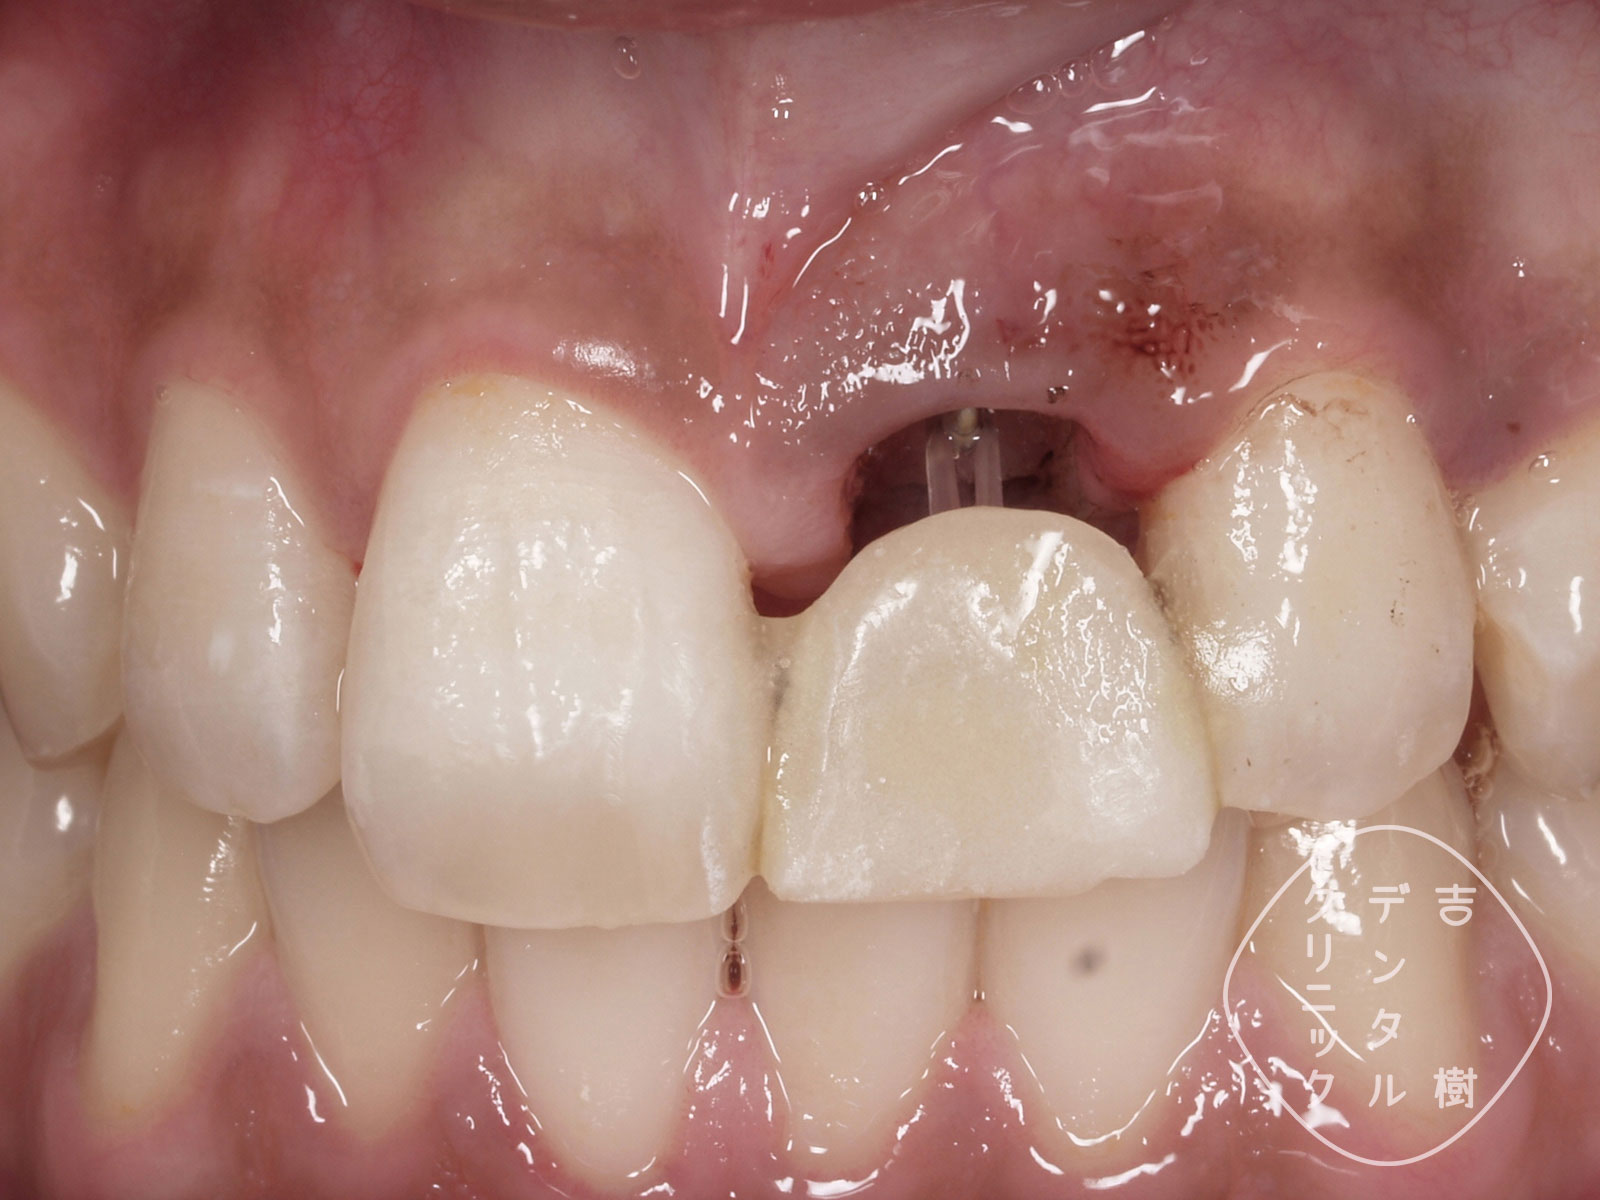

④歯の根を外側に引き出す、矯正治療を行う

⑤治療中は、接着材で被せ物を取り付ける

⑥歯の根が外側に引き出されてきた

⑦歯の根に土台を取り付けたところ

⑧被せ物を装着し、治療完了